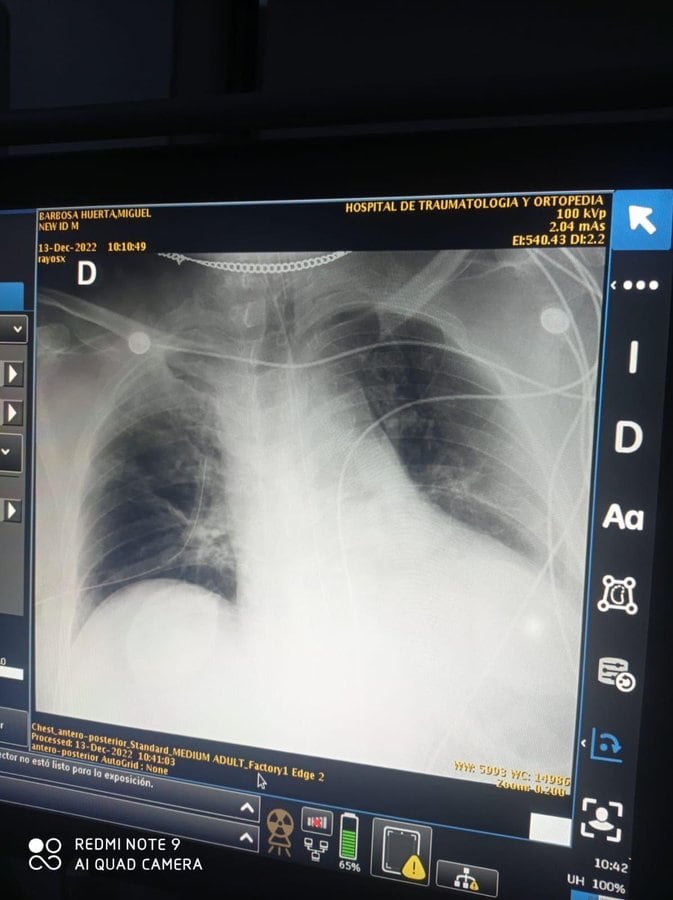

Los datos otorgados aseguran que en un primer momento, el traslado de Miguel Barbosa al Hospital de Traumatología y Ortopedía fue un error, pues el gobernador debió ser trasladado al Hospital Cívil de Puebla, donde cuentan con un área hemodinámica especializada en arterias, venas y corazón.

Asimismo, se indicó que los médicos que atendieron al gobernador en dicho Hospital habrían incurrido en una negligencia al “ponchar” el pulmón izquierdo de Barbosa.

Dicho argumento, acompañado de una radiografía, apunta que los médicos le habrían hecho un mal procedimiento a Miguel Barbosa, que terminó por perforarle el pulmón.

Siendo la acción que habría complicado de manera importante el estado de salud del gobernador, y que finalmente lo llevó a su muerte.